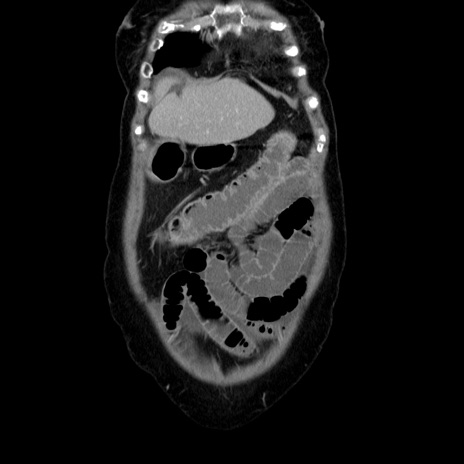

症例5(冠状断像)

【症例】70歳代女性

【主訴】お腹が張る

【現病歴】1週間くらい前から腹部膨満の自覚あり。昨日夜から増悪したため、本日救急外来受診。

【身体所見】意識清明、BT 36.5℃、BP 165/106mmHg、HR 80bpm、SpO2 98%、腹部:膨満、軟、自発痛・圧痛なし、触診にて不快感あり、腸蠕動音:減弱

【データ】WBC 12600、CRP 1.04